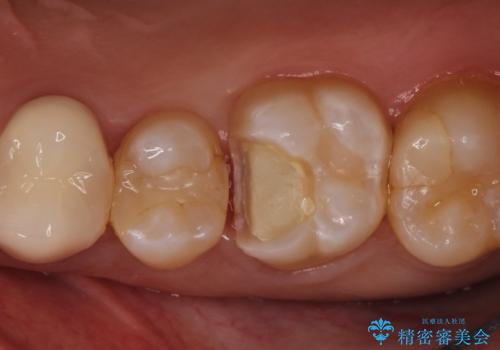

【VPT(歯髄温存療法)とセラミックインレー】深い虫歯でも神経を残したい

- 虫歯が大きく神経まで達していたので、VPT(歯髄温存療法)を行って細菌感染した部分の神経のみ取り除き、保存可能な神経は保存し被せ物はセラミックインレーで治療を行いました。

昔の歯科医療では神経まで虫歯が達している場合は神経を全て取らなければいけませんでした。しかし現代の歯科医療ではBio-C SealerやMTAセメントの開発により健康な神経を残せるようになりました。

Bio-C Sealerを塗布後、神経に優しい光重合型充填用レジン強化グラスアイオノマーセメントで裏層を行っています。

※術前に神経の状態の検査を行い、術中にもマイクロスコープにて神経の状態を直接確認したうえで残せると判断した場合に行っています。